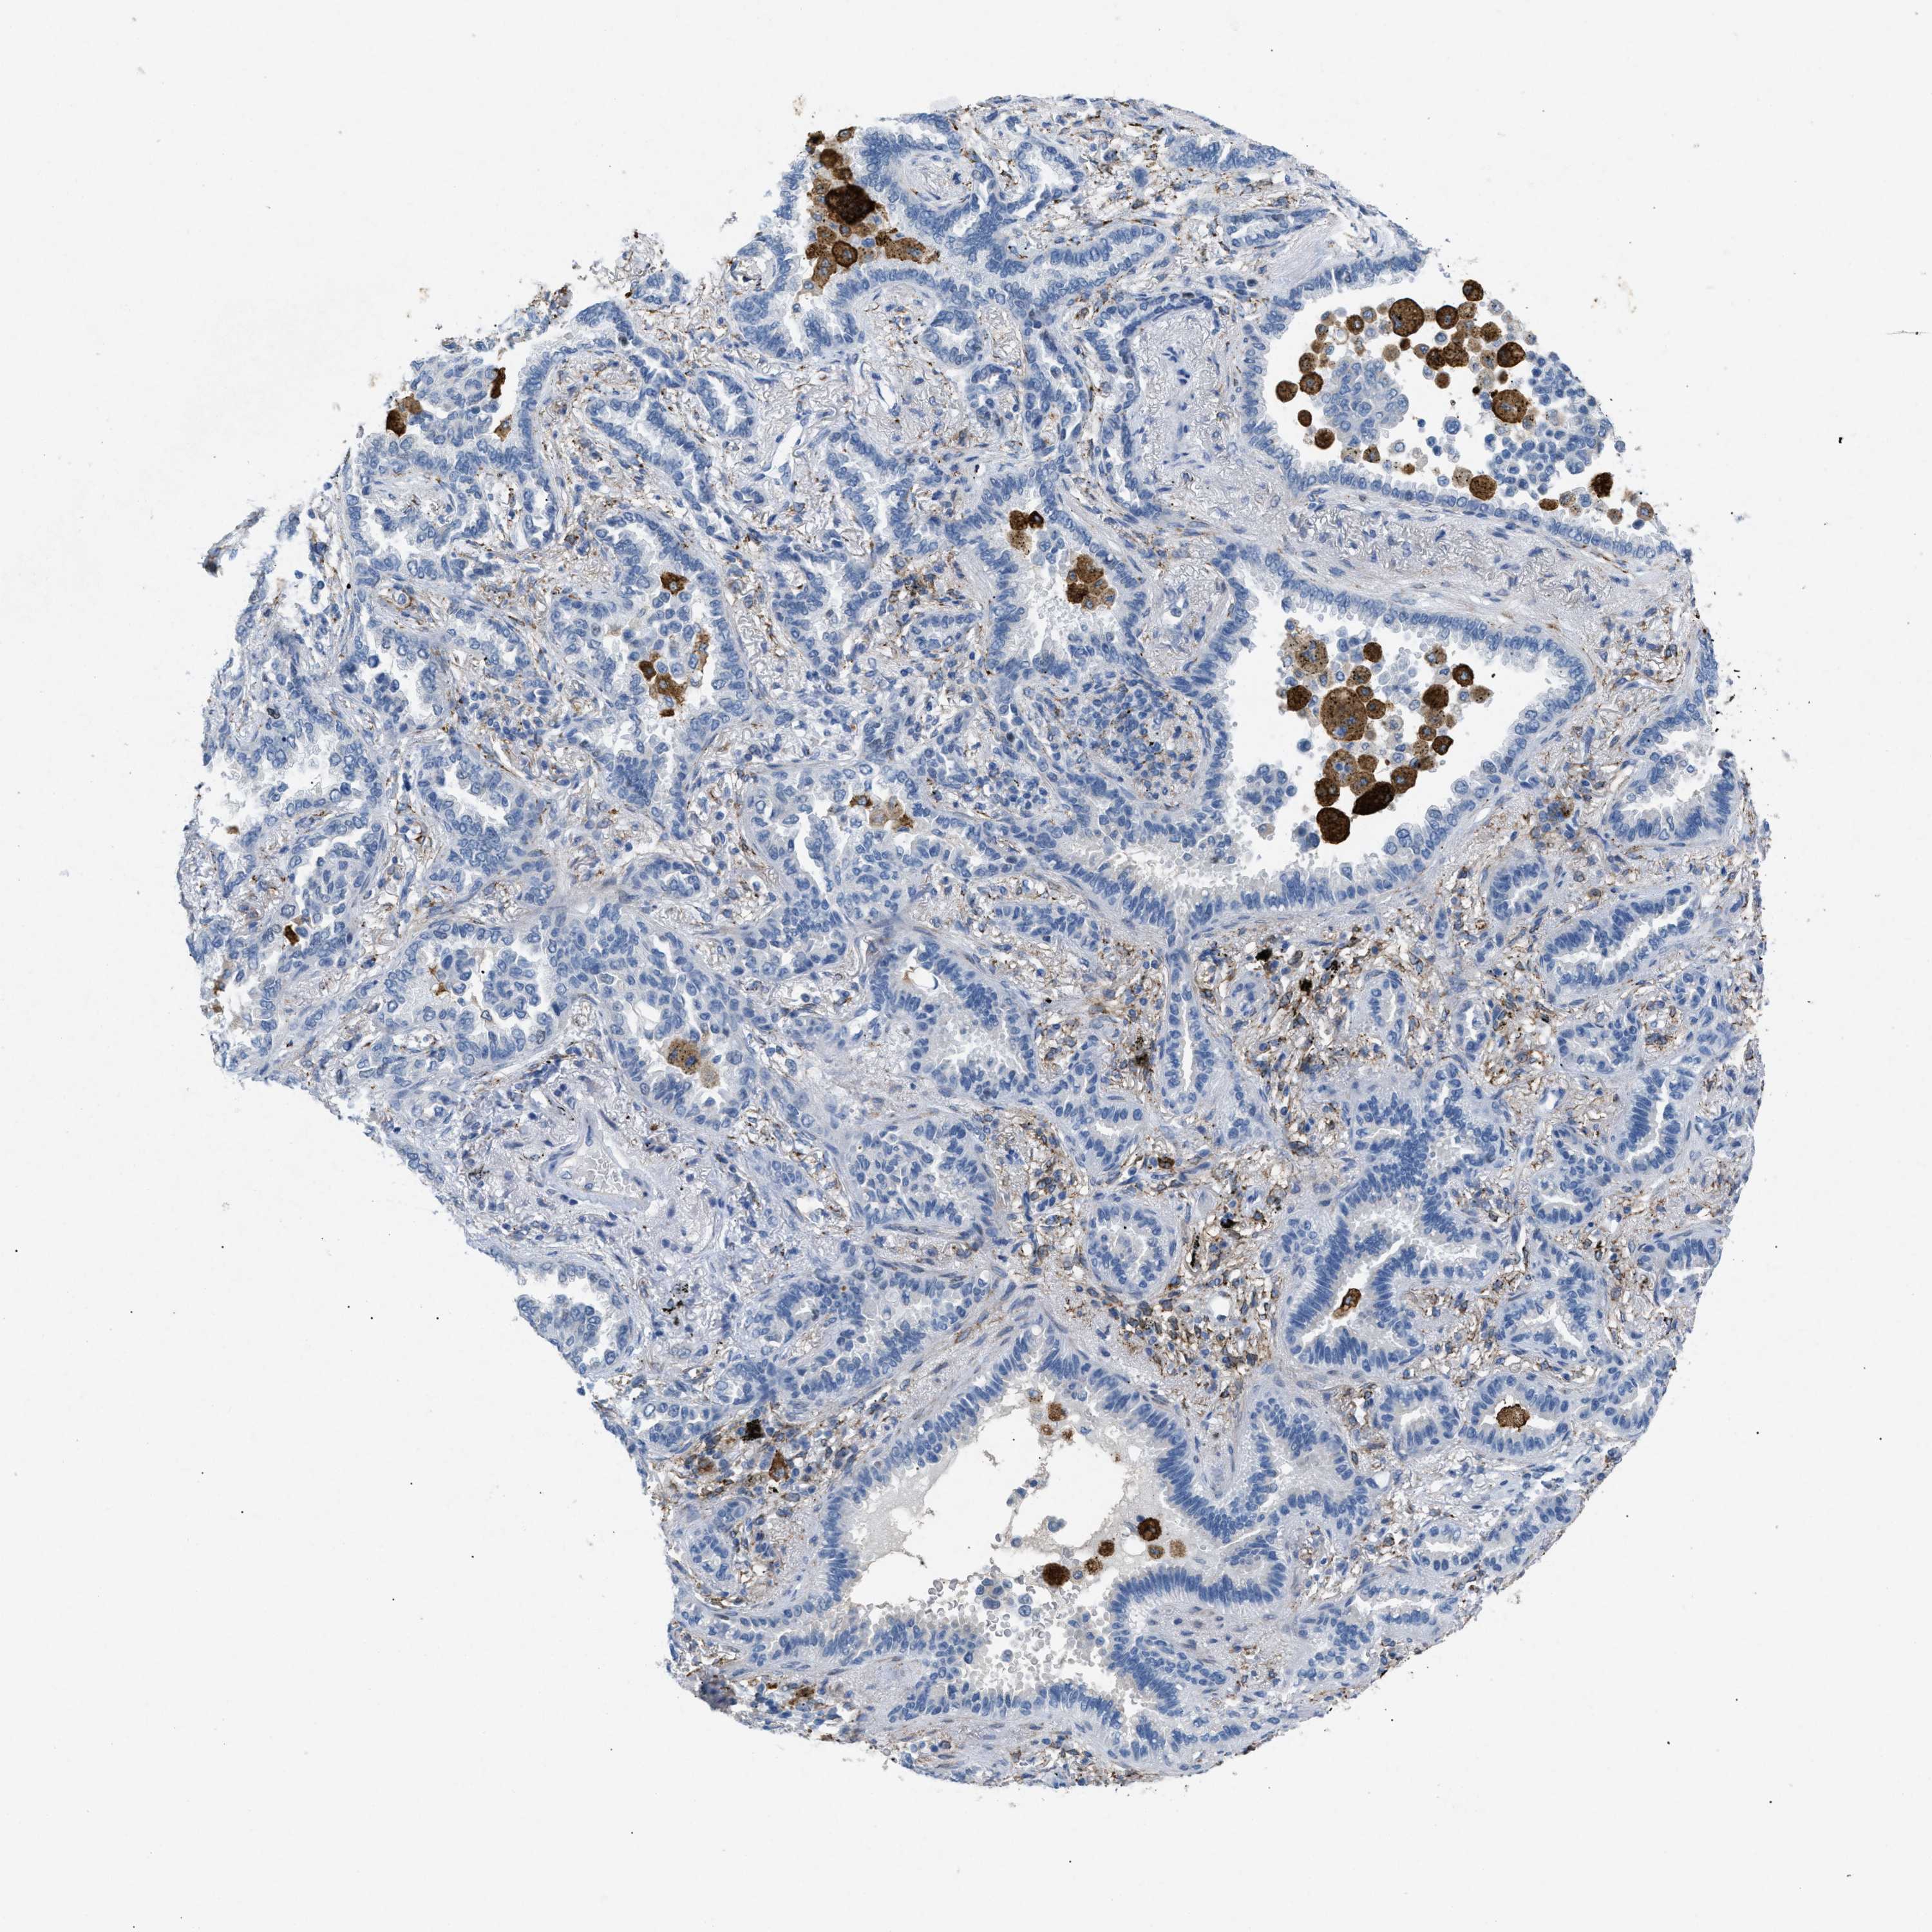

CANCER LUNG CANCER Show tissue menu

LUAD TCGA LUAD VALIDATION LUSC TCGA LUSC VALIDATION PROTEIN LUAD CPTAC PROTEIN LUSC CPTAC PROTEIN EXPRESSION